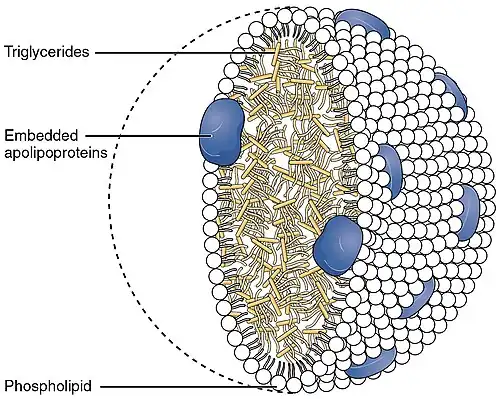

Cholesteryl ester transfer protein (CETP), also called plasma lipid transfer protein, is a plasma protein that facilitates the transport of cholesteryl esters and triglycerides between the lipoproteins. It collects triglycerides from very-low-density lipoproteins (VLDL) or chylomicrons and exchanges them for cholesteryl esters from high-density lipoproteins (HDL), and vice versa. Most of the time, however, CETP does a heteroexchange, trading a triglyceride for a cholesteryl ester or a cholesteryl ester for a triglyceride.